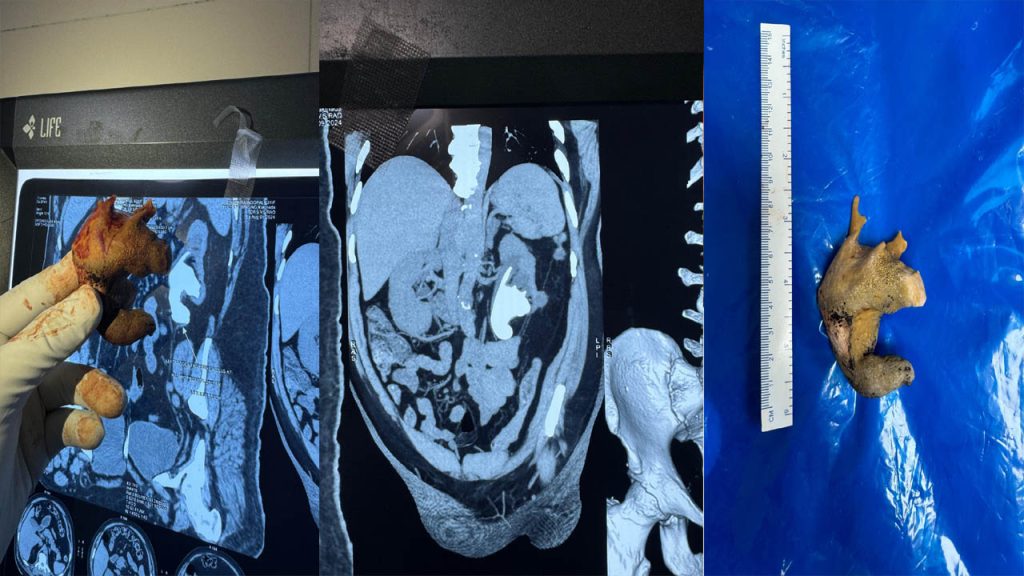

Visakhapatnam, September 2024: Kidney stones are usually small, but a rare and severe case recently emerged involving a large staghorn stone that filled an entire kidney in a 62-year-old patient from Visakhapatnam. These staghorn stones form through the crystallization of minerals over time and often go unnoticed because they do not obstruct urine flow, leading to late detection and treatment. Consultant urologist Dr. Amit Saple shared insights into this unique case.

The patient, a farmer, sought treatment at AINU Hospital after experiencing occasional pain in his left side. Ultrasound and CT scans revealed the large staghorn stone, and his kidney function was severely compromised, operating at only 18%, according to Dr. Saple.

Traditionally, such stones are removed either through a kidney puncture to break them internally or via open surgery with an incision. In this case, the medical team employed a laparoscopic pyelolithotomy, accessing the stone from the front of the abdomen instead of through the kidney. “This minimally invasive technique allowed us to remove the entire stone, including all its extensions, without breaking it,” Dr. Saple explained.